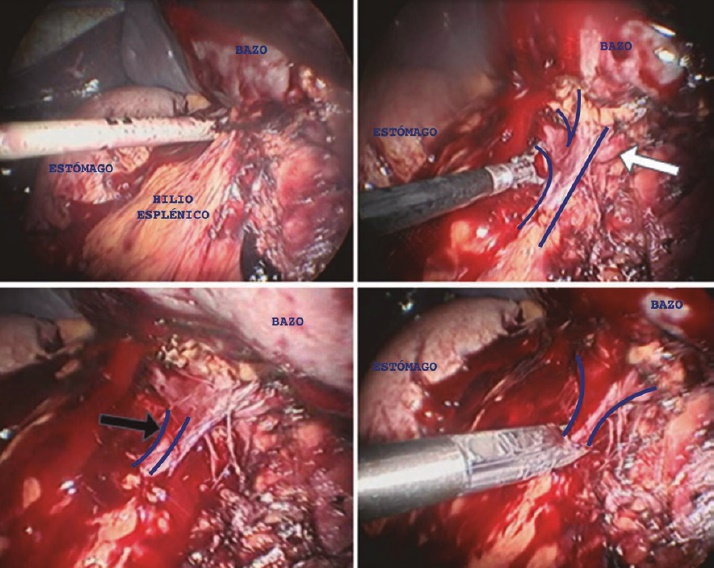

Se realizó laparoscopía diagnóstica y se inició disección del bazo liberando ligamentos lienocólico con energía ultrasónica (figura 5a), al igual que los ligamentos esplenorrenal (figura 5b) y esplenofrénico (figura 5c) y gastroesplénico (figura 5d). Se continuó la disección del hilio esplénico colocando grapas de titanio en la vena esplénica, y ligadura con nudo extracorpóreo con sutura monofilamento no absorbible de la arteria esplénica (figura 6). Se realizó la extracción completa de la pieza quirúrgica ampliando la incisión del puerto de trabajo. Se revisó la cavidad por tejido esplénico accesorio sin identificar, se verificó hemostasia y se colocó drenaje en lecho quirúrgico exteriorizándolo por incisión en línea axilar posterior.

Figura 6 Disección del hilio esplénico. Flecha blanca: arteria esplénica. Flecha negra: vena esplénica.